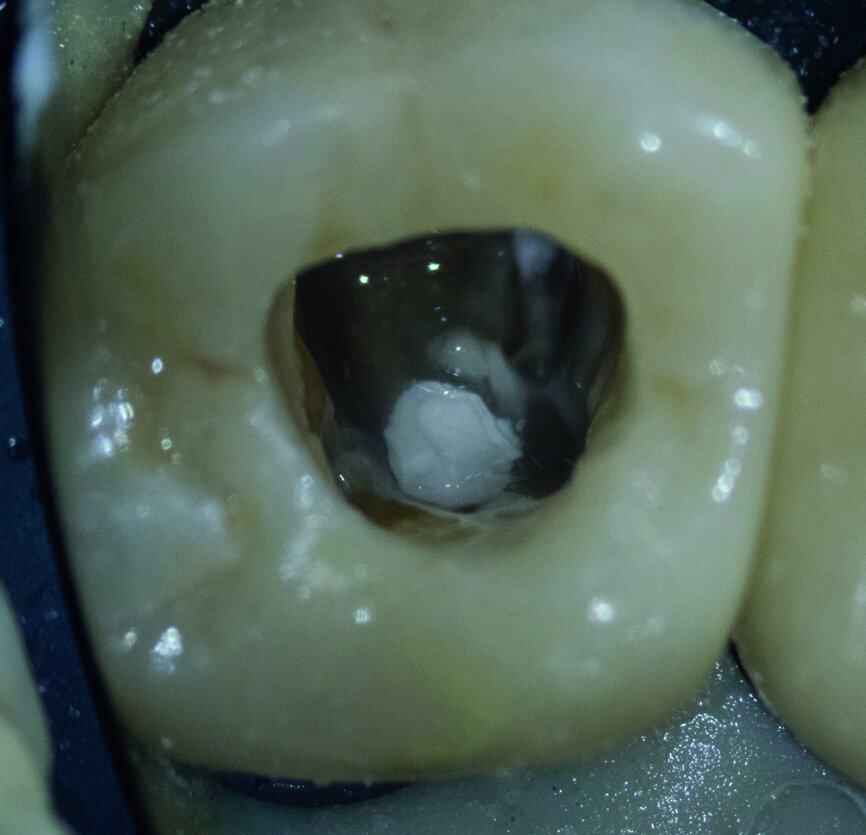

Fig. 3 : La perforation a été fermée avec un ciment hydraulique à base de silice.

Fig. 6 : Le ciment hydraulique à base de silice après sa prise complète.

Fig. 7 : L’excès de ciment a été éliminé autant que possible.

Fig. 8 : Dentine et ciment obturés avec G Premio BOND.

Au cours de la deuxième visite, l’excès de ciment hydraulique à base de silice a été éliminé autant que possible (Figs. 6 et 7) puis la dentine a été obturée au moyen de G-Premio BOND avant une désinfection par NaClO, selon le protocole de ≪ scellement endodontique immédiat (IES) ≫,1 qui est similaire au protocole de scellement dentinaire immédiat (IDS) (Fig. 8). Cet adhésif universel doit être sèche à l’air sous pression élevée. Il est idéal pour les cavités endodontiques profondes car il n’y a pas d’accumulation de l’adhésif sur le fond cavitaire.